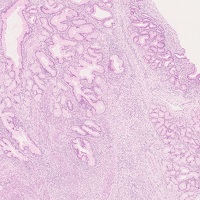

【子宮頚部/悪性腫瘍】

粘液性腺癌